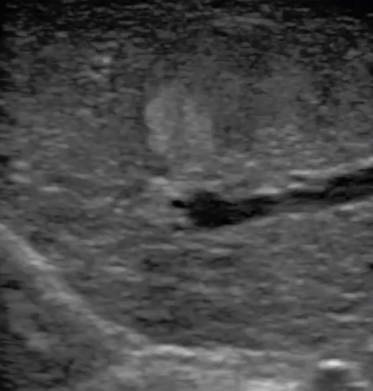

腹腔鏡超聲是超聲技術(shù)和腹腔鏡技術(shù)的融合,腹腔鏡超聲降低了對超聲探測深度的要求。由微小切口進入手術(shù)部位,多角度彎曲可選擇,降低手術(shù)難度及風(fēng)險;與受檢組織器官直接接觸,有效避免氣體干擾。

應(yīng)用科室:麻醉科、手術(shù)室、普外科、泌尿外科、婦產(chǎn)科、腫瘤科、介入科等

腹腔鏡下 肝臟占位